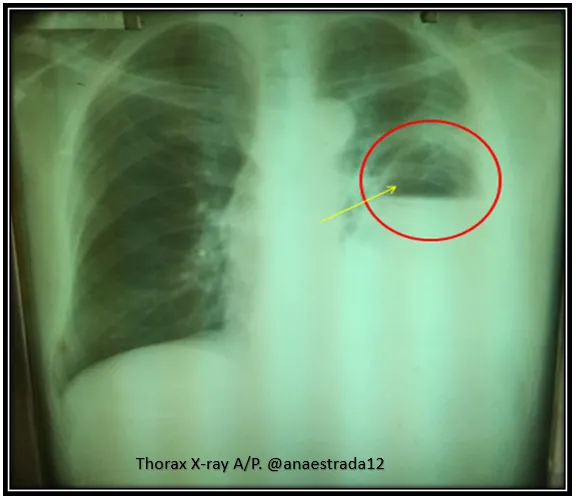

The diagnosis is confirmed by X-ray and chest CT scan (Rx Tx, TC Tx).

Where the pathognomonic sign of this entity in the chest X-ray is the presence of a cavity with hydroaeréo level.